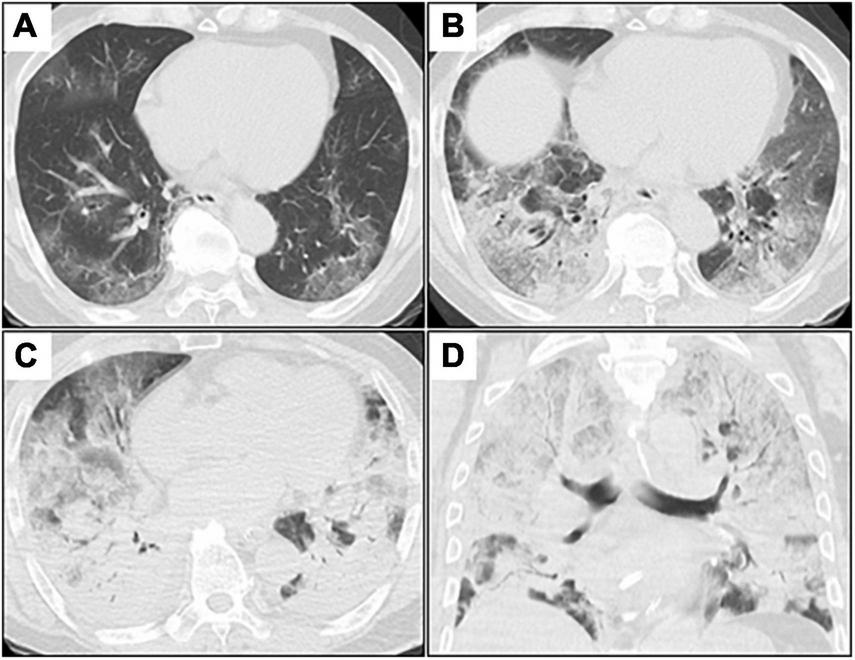

A 73-year-old man was admitted to our hospital for general fatigue, presenting with symptoms of productive cough and fever for 4 days. He was a former smoker who had smoked 20 cigarettes a day for 20 years but had no pre-existing lung disease. His vital signs were as follows: blood pressure, 115/80 mmHg; heart rate, 110 beats/min; blood temperature, 36.2°C; respiratory rate, 24 breaths/min; and oxygen saturation, 90% on ambient air. Hematological examination revealed the following: white blood cell count, 2,600 cells/μL; differential count, 65.5% neutrophils, and elevated levels of C-reactive protein, 5.13 mg/dL (normal < 0.14 mg/dL); D-dimer, 10.1 μg/mL (normal < 1.0 μg/mL); LDH, 384 U/L (normal range, 124–222 U/L); and serum ferritin, 1,776 ng/mL (normal range, 20–200 ng/mL). SARS-CoV-2 infection was confirmed through reverse-transcriptase polymerase chain reaction (RT-PCR). Chest computed tomography (CT) on admission revealed patchy ground-glass opacities in both peripheral lungs, indicative of interstitial pneumonia (Figure 1A). A monoclonal antibody therapy directed against the spike protein of SARS-CoV-2 (casirivimab–imdevimab, 600/600 mg as a single intravenous dose) was initiated for moderate COVID-19 pneumonia; however, it was ineffective. On day 3, the patient continued to worsen clinically with progressive ground-glass opacities observed on the follow-up chest CT (Figure 1B). Thus, oxygen was administered with a high-flow nasal cannula (HFNC) at 40 L/min, with FiO2 titrated for oxygenation. In addition, we used a combination of oral dexamethasone (6 mg daily for 10 day) and IV remdesivir (200 mg, followed by 100 mg daily for 5 day), together with tocilizumab infusion (480 mg daily for 1 day). The chest CT on day 7 of admission revealed extensive ground-glass opacities, and diffuse consolidation with air bronchogram showing anteroposterior gradient in both the lungs, consistent with that of ARDS (Figures 1C,D). The patient developed severe hypoxemia of SpO2 80%, despite HFNC oxygen therapy (FiO2 1.0, 40 L/min), requiring intubation for respiratory insufficiency and IMV in the intensive care unit. The PaO2/FiO2 ratio was 120, suggestive of moderate ARDS. The IMV in the prone position was applied at a tidal volume of 6.6 mL/kg, positive end-expiratory pressure of 15 cm H2O, plateau pressure of 14 cm H2O, and respiratory frequency of 28/min. On day 15, a catheter-related bloodstream infection caused by Enterobacter aerogenes led to bacterial septic shock, consequent acute kidney injury and disseminated intravascular coagulation, requiring vasopressors, continuous renal replacement therapy, steroid infusion (Solu-Medrol 40 mg, daily for 16 day), and heparin infusion for 7 day. In addition, broad-spectrum antimicrobial treatment with meropenem (1 g/day IV for 10 day) was initiated, followed by antimicrobial de-escalation based on antimicrobial susceptibility test results (ceftriaxone, 4 g/day IV for 12 day). The chest CT on day 22 of admission revealed several lung cysts related to diffuse alveolar damage, predominantly on the right lung. Note the air-filled cystic lesion communicating to the segmental bronchus, was suspicious of a bronchopleural fistula (BPF) (Figure 2A). Follow-up RT-PCR confirmed SARS-CoV-2 negativity. On day 26, since the patient’s clinical status gradually improved, he was weaned off the IMV and extubated. The patient’s clinical condition remained stable thereafter; however, consecutive chest CT scans revealed progressive increase in size and number of lung cysts with a tendency to fuse with each other (Figure 2B). Two days later, the patient presented with dyspnea and severe chest pain. His vital signs were as follows: blood pressure, 90/70 mmHg; heart rate, 124 beats/min; respiratory rate, 38 breaths/min; and oxygen saturation, 83% on ambient air. The breath sounds were significantly diminished on the right side. Chest CT revealed a large right pneumothorax due to collapsed cysts with mediastinal shift, strongly suggestive of tension pneumothorax (Figure 2C). Air leaks had persisted despite two consecutive 20-Fr chest drain insertions (Figure 2D). On day 53, autologous blood pleurodesis (ABP) procedure was performed (100 mL, twice), but PALs were still observed. Moreover, collected material from chest cavity drainage tube was purulent, and CT findings on day 70 of admission were consistent with those of empyema (Figure 3A). On day 76, we attempted to facilitate healing of the PALs by inserting an Endobronchial Watanabe Spigot (EWS), a type of silicone bronchial blocker. Leak isolation performed via sequential balloon occlusion of the segmental bronchus using a bronchoscope revealed that the main source of the PALs was located in the right B8b segment, which was confirmed by an immediate reduction in air leaks on deploying a medium-sized EWS (Novatech, La Ciotat, France), and the procedure was completed (Figure 3B). Although air leaks recurred after an hour, bronchoscopy did not show any displacement of the implanted EWS, suggesting that the PALs were presumably due to myriad alveolopleural fistulas (APFs). Subsequent thoracoscopy revealed that the empyema cavity was too narrow for thoracoscopic manipulation. Therefore, minimally invasive open-window thoracostomy (OWT) using a wound edge protector was performed to eliminate PALs (Figure 3C and Supplementary Figure 1A). The incision length was 7 cm and surgical time was 105 min. Nine days after a dressing change, we clinically confirmed the cessation of air leaks. On day 90, negative-pressure wound therapy (NPWT) with a vacuum-assisted closure (VAC) device (KCI Medical Products, Winborne, Dorset, United Kingdom) was performed (Figure 3D). The pleural cavity was filled with GranuFoam (VAC Granufoam; KCI Medical, San Antonio, TX, United States), and covered with semipermeable films. Continuous suction was initially started at a negative pressure of 50 mmHg, and then maintained at a maximum negative pressure of 125 mmHg, alongside careful monitoring of the lung tissue damage. The dressings were changed twice per week. The patient well-tolerated these serial procedures, and experienced relief from dyspnea. NPWT for 28 days allowed re-expansion of the collapsed lung and enhanced wound granulation, resulting in closure of the thoracic cavity without the need for muscular flaps (Figures 3E,F and Supplementary Figures 1B-E). The postoperative course was uneventful. However, on day 110, the patient developed an extrapulmonary complication of a subcortical hemorrhage of the right parietal lobe, for which endoscopic hematoma evacuation was performed on day 125. Eventually, the patient was transferred to another hospital for further rehabilitation on day 158. At the 1-year follow-up, no recurrence of pneumothorax was observed. We present a timeline of the case in Figure 4.

Figure 1. Serial chest CT images after admission. (A–C), axial images; (D), coronal image. (A) Initial chest CT shows patchy GGOs in bilateral peripheral lungs. (B) Chest CT on day 3 (day 3 of admission) shows extensive and diffuse GGOs with patchy consolidation. (C,D) Chest CT on day 7 shows diffuse consolidations worsening from GGOs with air bronchogram in both the lungs. CT, computed tomography; GGOs, ground-glass opacities.